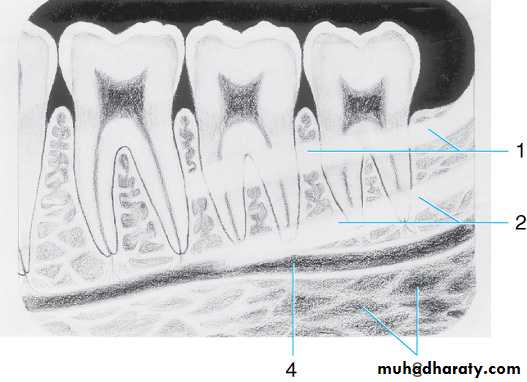

Drawing of mandibular molar area. Drawing illustrates the (1) ext oblique ridge, (2) mylohyoid or internal ridge, (3) submandibular fossa, and (4) mandibular canal

Radiograph of mandibular molar area. Shown are the (1) oblique ridge (buccal), (2) mylohyoid ridge (lingual) (3) mandibular canal, and (4) submandibular fossa

Radiograph of mandibular molar area. Shown are the

(1) Ext oblique ridge,(2) mylohyoid or internal oblique ridge,(3) mandibular canal and

(4) submandibular fossa